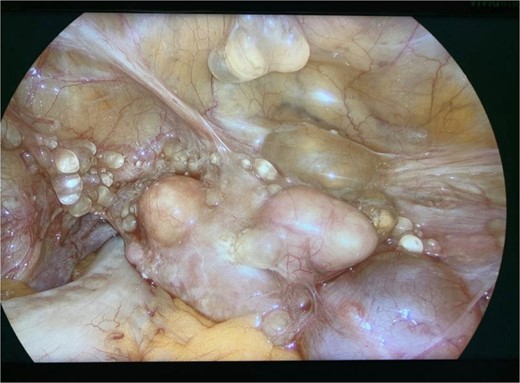

Diagnostic laparoscopy demonstrated multiple cystic lesions throughout the abdomen and pelvis (Figs 3 and 4). The gross appearance of these cysts was consistent with mucinous carcinomatosis. Laparoscopic excisional biopsy of several lesions was performed. Frozen section analysis revealed mucin but did not reveal evidence of metastatic adenocarcinoma. Colectomy was deferred due to concern for carcinomatosis, as if confirmed, she would likely be treated with neoadjuvant chemotherapy, restaging, followed by cytoreductive surgery (to include synchronous right colectomy) with heated intraperitoneal chemotherapy.

Intraoperative view of the pelvis: multiple cysts involving the peritoneum.